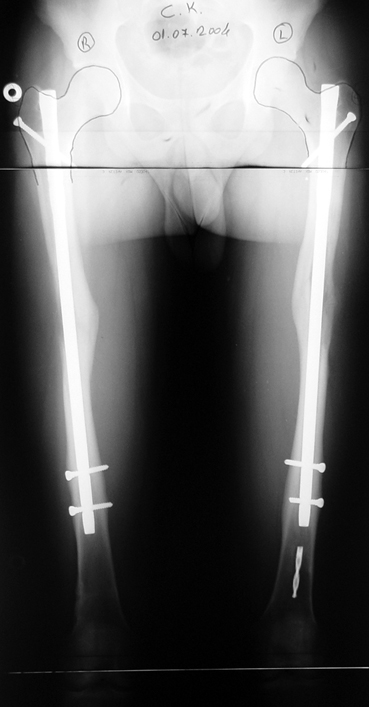

Postoperative care: Distraction is commenced at day 10. 0,25 mm of lengthening is perfomed 4 times daily (every 6 hours). Hip and knee joint motion exercises begin at 1-2. day postoperatively. For many years, the treatment of lower extremity shortness has been very hard for the patient and the surgeon. The techniques developed after the introduction of Ilizarov’s distraction osteogenesis concept have pioneered a new era, and have been considered to be procedures in which previous complications are encountered much less frequently.

In selected cases, we prefer to use a combination of a unilateral dynamic axial fixator and an interlocked intramedullary nail, in order to protect the length and alignment after the completion of the lengthening procedure. As a prerequisite for this technique, the narowest diameter of the medullary cavity shall be wider than 7 mm and the length of the nail segment distal to the osteotomy site shall be at least 8 cm. after the completion of the lengthening procedure.The intramedullary nail neutralizes shear and bending forces on femur during lengthening, shortens external fixation time, and protects newly formed bone against fractures. In our series, subtrochanteric osteotomy was performed in one case. No varus angulation occured despite the intramedullary nail.

Ilizarov stressed the significance of endosteal blood circulation for distraction osteogenesis. Although we placed the intramedullary nail after reaming the femur in all cases, the time for callus formation was not longer than expected. Thus we found that there is no slowing in the rate of new bone formation due to disruption of medullary blood flow. The rationale of this finding is revascularization that occurs following reaming of the medullary cavity, the fixation stability with the intramedullary nail and early functional weight bearing. The potential disadvantages of a combined use of external and internal fixation metods are increased blood loss, intramedullary infection, risk of fat embolism and excessive metal load.The most fearsome complication is a deep intramedullary infection (panosteomyelitis) triggered by pin tract infection.No such complication was encountered in our series. In order to avoid this complication, after the completion of lengthening the nail shaill be interlocked from the medial side, and contact of internal and external fixator pins shall be avoided.

The combination of intramedullary anil and dynamic axial external fixator is harder as a technique than Standard Ilizarov applications. However, it is stil appealing due to the following advantages: shortening of the duration of external fixation, protection against refracture, early rehabilitation, gaining maximum range of motion and daily quality of life. These advantages are more important than disadvantages such as increased cost, increased blood loss and potetntial deep infection. All in all, we believe that the technique of femoral lengthening over an intramedullary nail is a safe and reliable method and provides advantages over standard Ilizarov aplications.